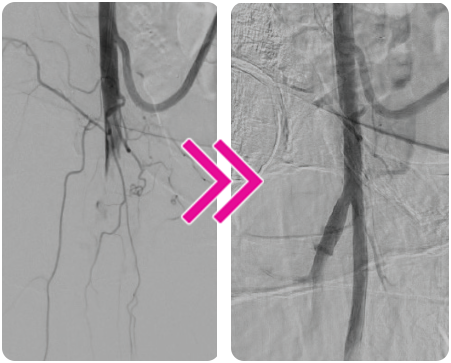

Successful Removal of an SMA Embolus With the Pounce™ Thrombectomy System

Nate Mohr, MD and Dennis Fry, MD

A 71-year-old man presented to the emergency department (ED) complaining of ongoing abdominal pain. Two days prior, he had visited the ED for a CT scan complaining of acute onset of abdominal pain in the morning. The CT scan was read as diverticulitis, and the patient was sent home on antibiotics. However, his symptoms continued to worsen, marked by increased bloating, abdominal distention, chills, and diarrhea, compelling him to seek urgent medical attention again.